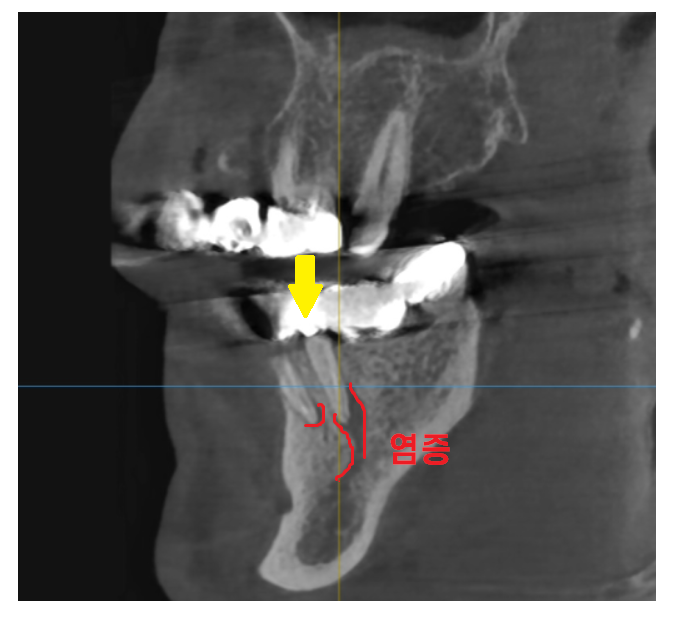

23.06.27

ct를 찍어 확인해보니

콧물 흐르듯 염증도 주루룩...

씌운 치아 통증 해결을 위해서는

발치한다.

강일동 임플란트한다.